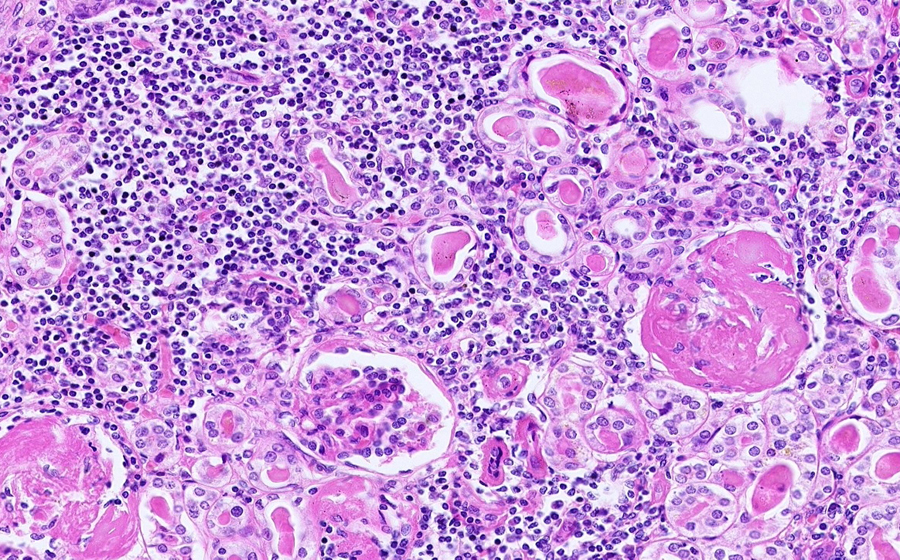

Image 4 - 100X

Slide 3 - Image 4